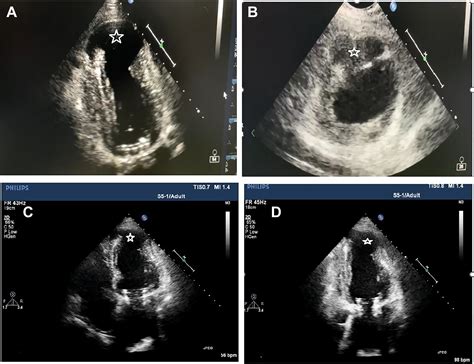

• Echocardiogram: This uses sound waves to create images of the heart, allowing doctors to visualize the aneurysm and assess its size and location.

• left ventricular aneurysm vs pseudoaneurysm